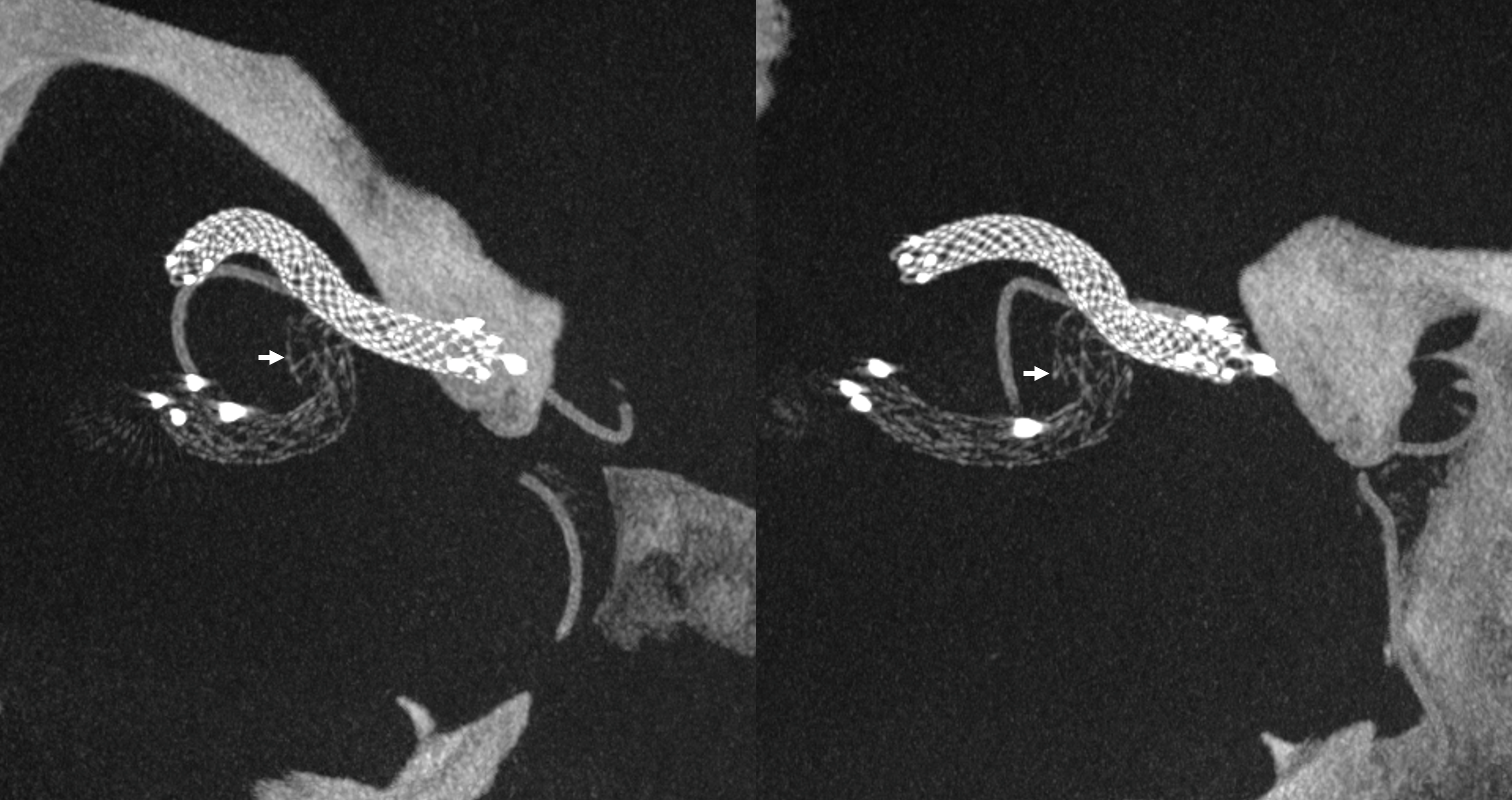

Noncontrast Vaso-CT, 22 cm FOV 20 seconds acquisition, followed by a secondary reconstruction with 50% FOV and 5123 resolution; Thick MIP.

Wide neck MCA trifurcation aneurysm.

Y stenting with Atlas and Lvis Evo, in emergency. The Atlas diameter was too large because of the temporary limited availability in our centre; we can clearly see the struts of the Atlas too open at the level of the aneurysm neck (arrow). Even the microcatheter for coiling is fully visible jailed by the Lvis Evo in M1

The injection of contrast medium (250 mg/ml, 50% dilution, manual injection, same reconstruction protocol as previous images) reduces the visibility of the struts — an important point to consider. Not everything is always the same contrast dilution, same injection rate, etc. etc. — you need to know how to vary every parameter to achieve desired results.